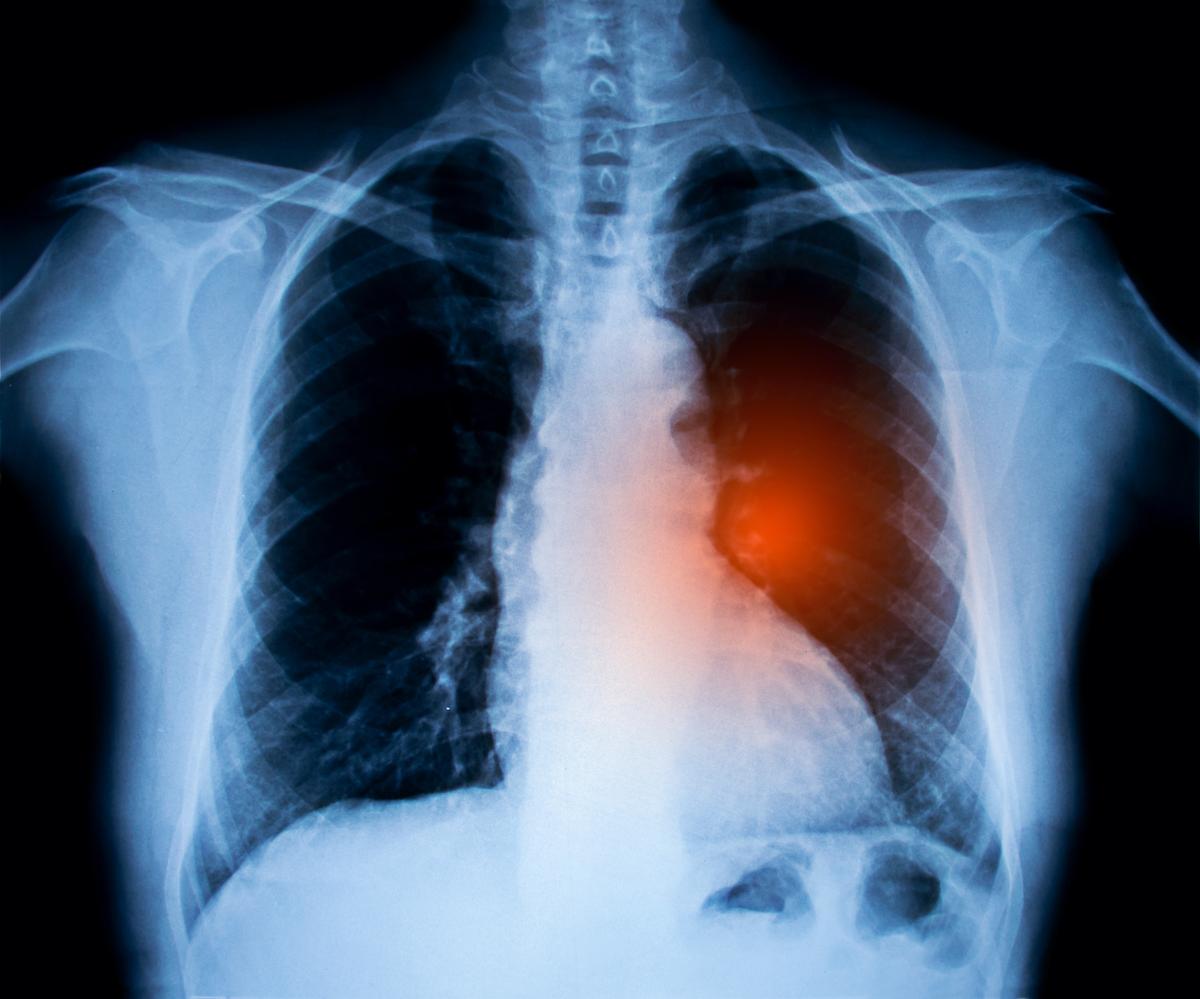

A nearly decade-long study revealed that a once-a-day pill can reduce the risk of death from lung cancer by more than half, offering hope for improved patient outcomes and potentially saving millions of lives.

Recently published in the New England Journal of Medicine (NEJM), the research involved 682 patients, including those diagnosed with non-small cell lung cancer (NSCLC), which accounts for 80 to 85 percent of all diagnosed lung cancers.